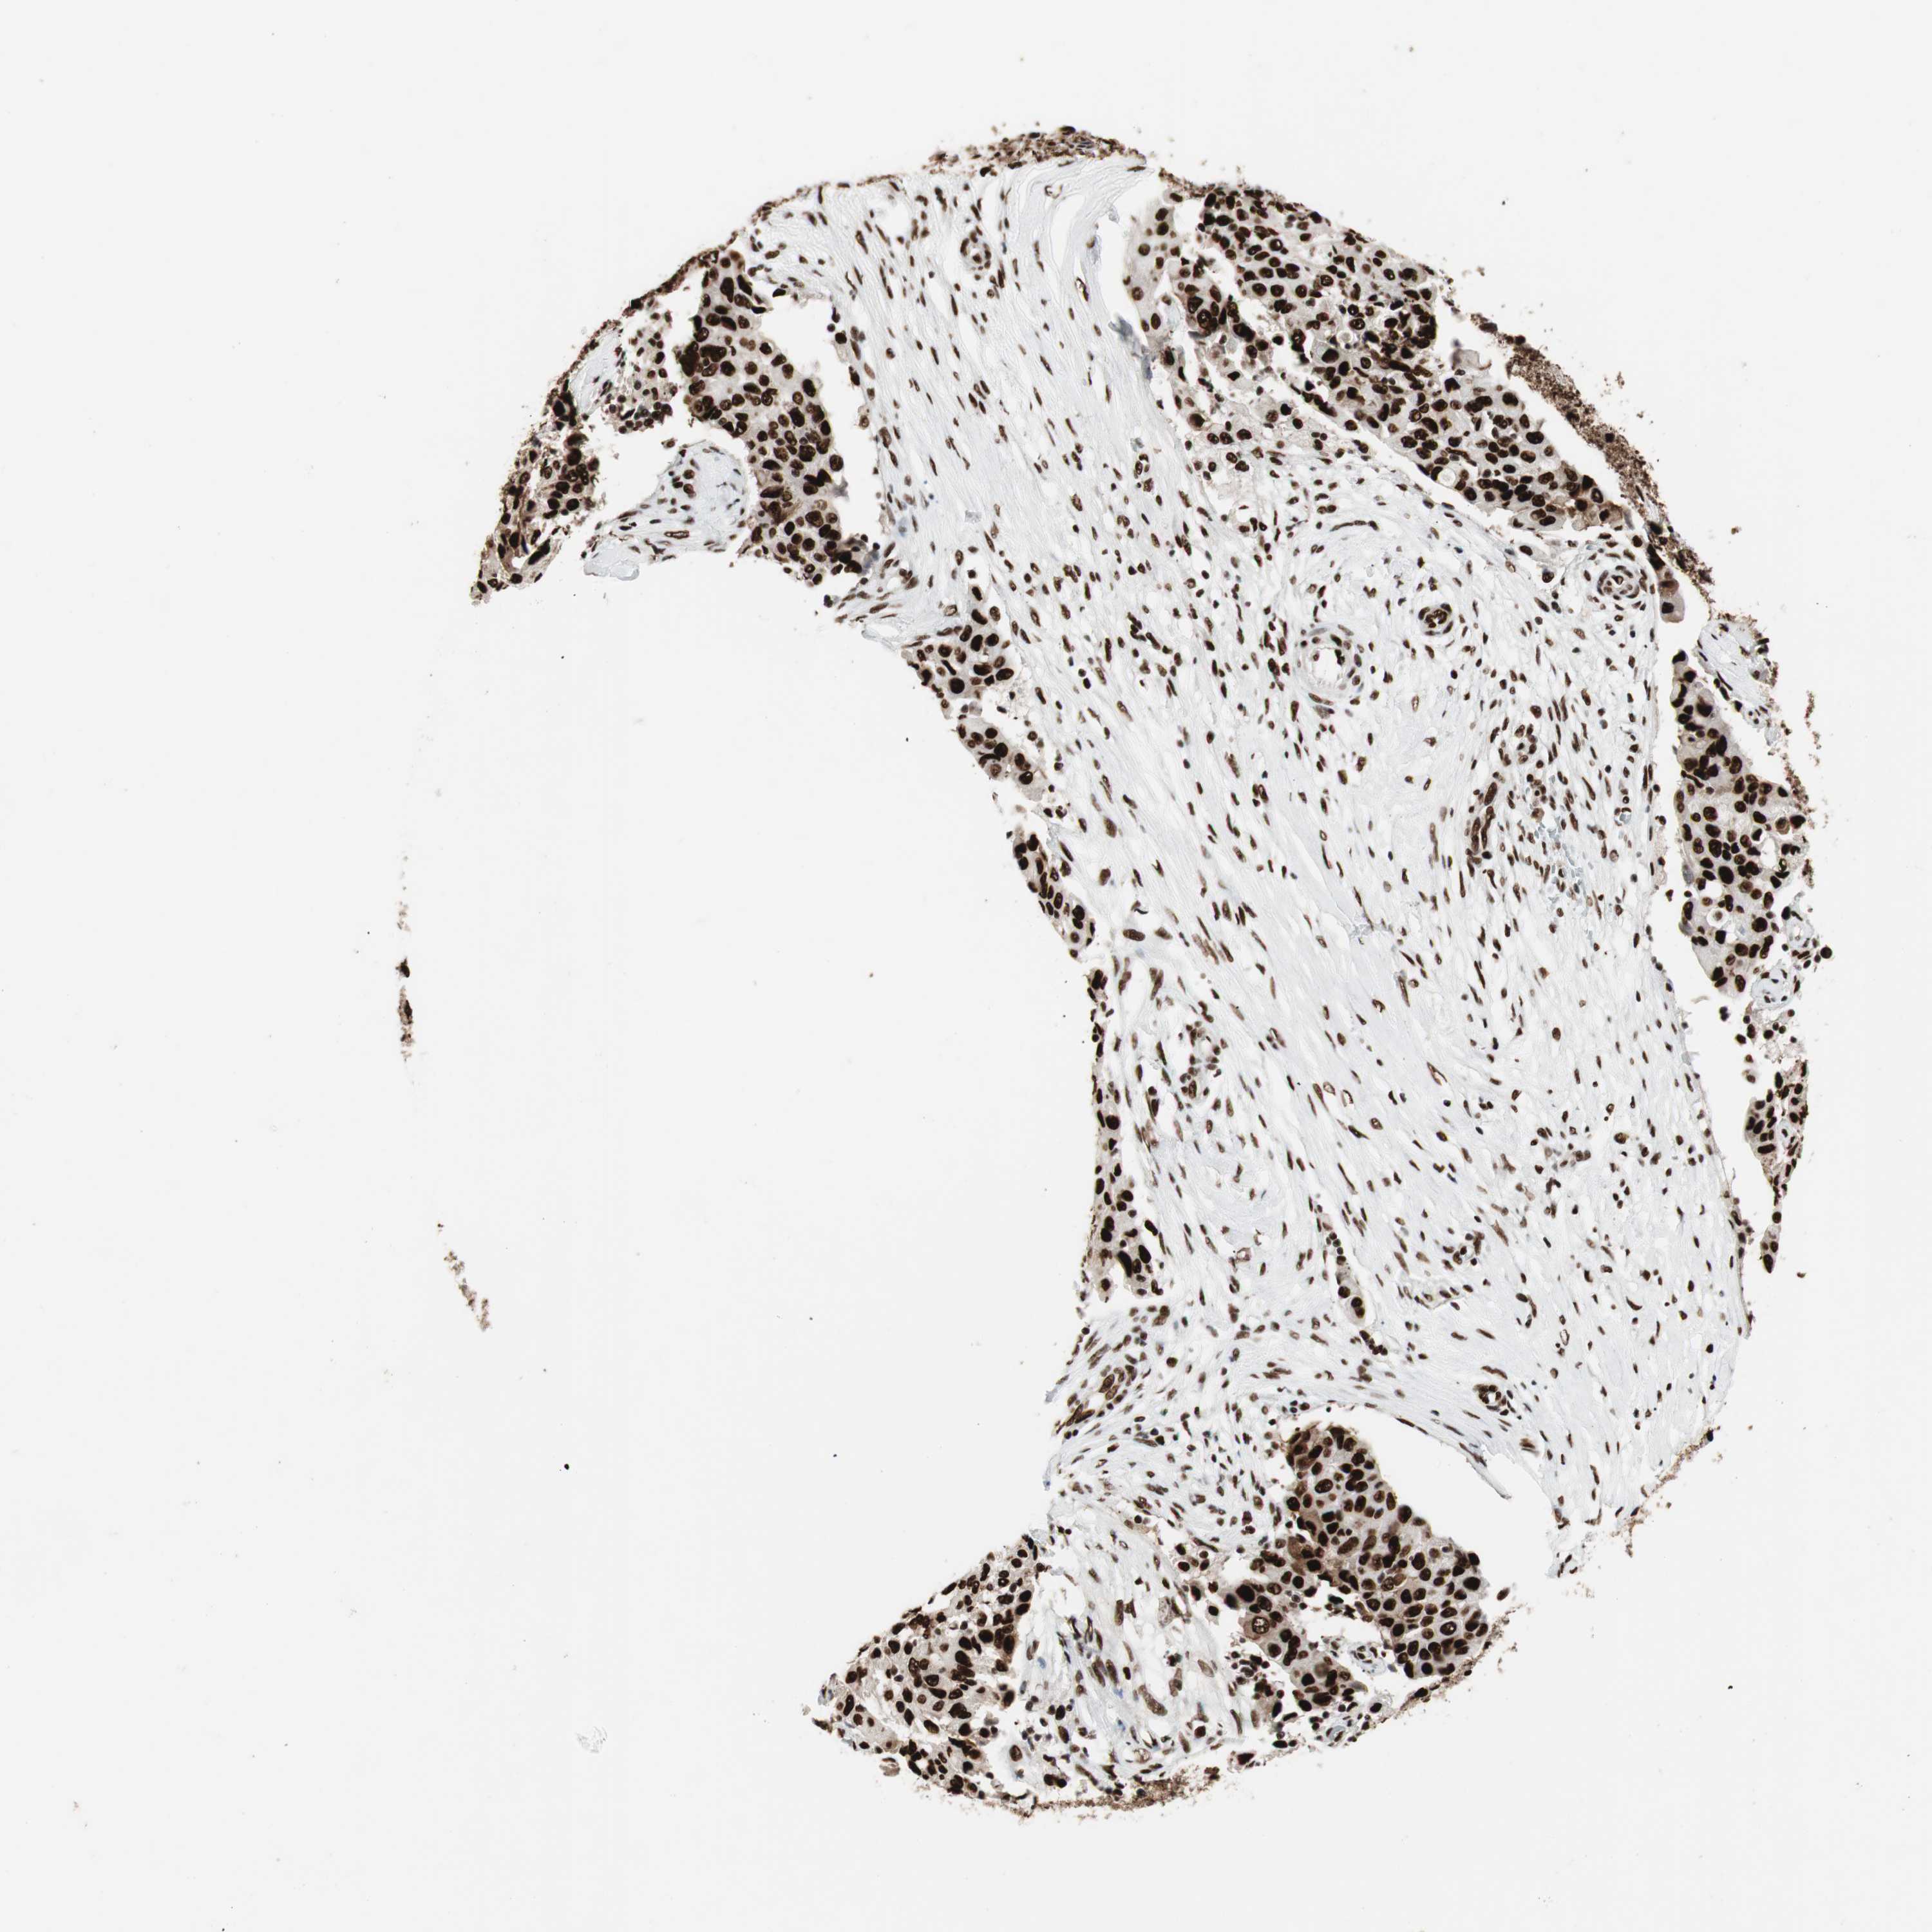

OVARIAN CANCER - Protein expressioni

A mouse-over function shows sample information and annotation data. Click on an image to view it in a full screen mode. Samples can be filtered based on level of antibody staining by selecting one or several of the following categories: high, medium, low and not detected. The assay and annotation is described here.

Note that samples used for immunohistochemistry by the Human Protein Atlas do not correspond to samples in the TCGA dataset.

Antibody stainingi

Antibody staining in the annotated cell types in the current human tissue is reported as not detected, low, medium, or high, based on conventional immunohistochemistry profiling in selected tissues. This score is based on the combination of the staining intensity and fraction of stained cells.

Each image is clickable and will lead to virtual microscopy that enables deeper exploration of all samples and also displays staining intensity scores, fraction scores and subcellular localization as well as patient and tissue information for each sample.

Antibody HPA012510

Antibody CAB008388

Staining

High

Medium

Low

Not detected

Intensity

Strong

Moderate

Weak

Negative

Quantity

>75%

75%-25%

<25%

None

Location

Nuclear

Cytoplasmic/membranous

Cytoplasmic/membranous,nuclear

Cystadenocarcinoma, serous, NOS

Carcinoma, endometroid

Cystadenocarcinoma, mucinous, NOS

Carcinoma, NOS